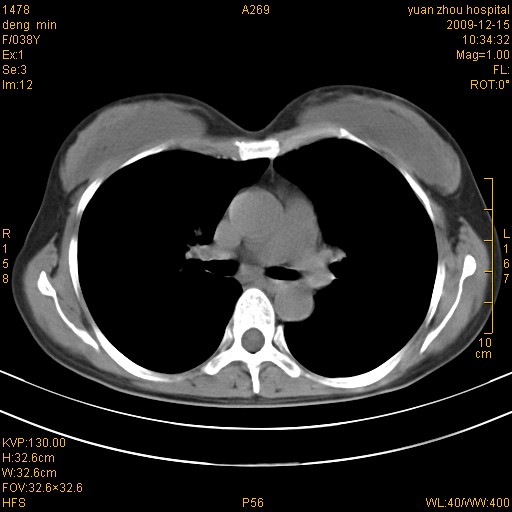

标题: CT23919:F38Y 咳嗽月余 [打印本页]

标题: CT23919:F38Y 咳嗽月余

支扩并感染

支扩感染

右肺中下叶、左肺上叶舌段及左肺下叶支气管扩张合并感染。